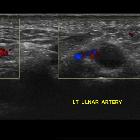

Radiographic features

Angiography

- “corkscrew” or beaded irregular appearance distal ulnar artery

- aneurysm formation

- occlusion of the ulnar artery segment overlying the hook of the hamate

- occluded or under-filled distal digital arteries in an ulnar artery distribution